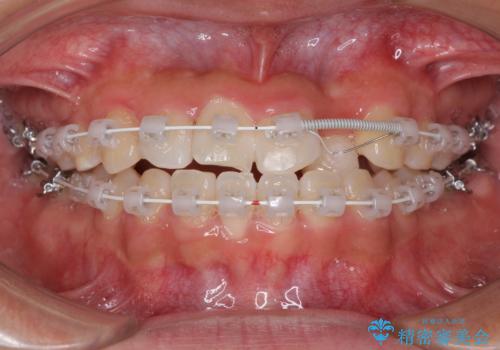

- 矯正装置

- 審美装置

今後はすり減ってしまった歯の形をセラミッククラウンで改善したいとのことで、クロスバイトが改善し咬みやすくなった時点で装置を外すこととしました。

1年で治療を終えることができ、患者様には大変満足していただきました。